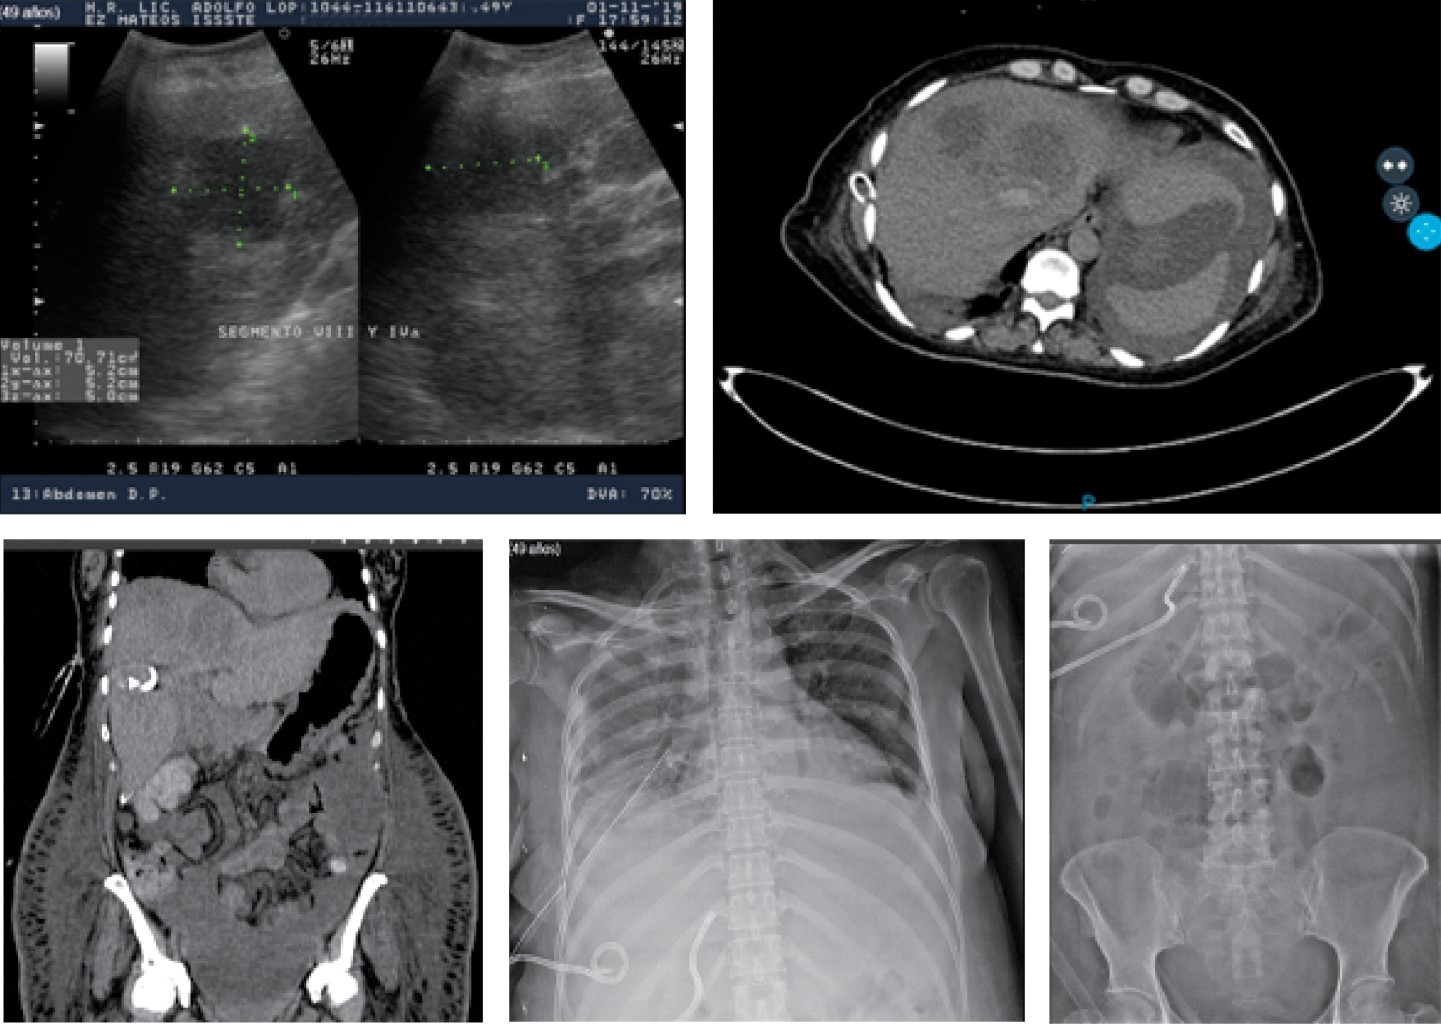

In intensive care, a new abdominal USG was performed (1-XI-19) and then mobilized to the Radiology Department to perform a simple and contrasted CT of the abdomen, performing a first puncture that same day and due to the lack of drainage and no decrease in the collection, a second puncture was performed on November 7, 2019, leaving two pigtails with 8 Fr catheters in two of the major collections (Figure 6).

The oral route was restarted with a liquid diet and porridges, gradually withdrawing total parenteral nutrition and having ceded fever, improved her body fluid redistribution, and hepatic drains expenses decreased to less than 40 cm3 in 24 hours; the patient was discharged home on 20-11-2019 with cephalexin 500 mg c/6 hours, orally for 15 more days and monitoring of the remaining small hepatic collections with monthly USG for three months in the outpatient clinic (Figure 7).